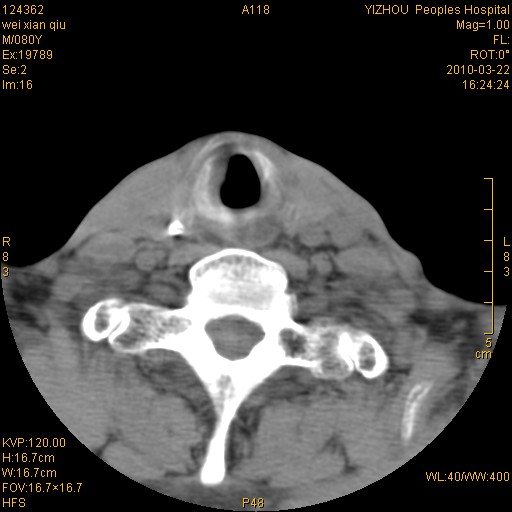

标题: CT25263:喉部占位?

男,80岁.声嘶三月余.

右侧声们下区新生物

右侧声们下区新生物,建议行喉镜检查(活检)进一步明确诊断。